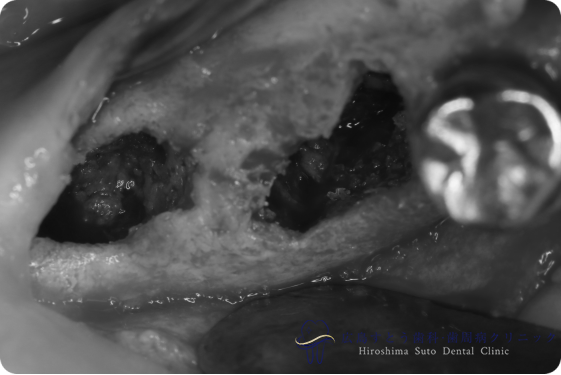

術中(手術中の写真)

手術中の状態:骨移植前

骨移植後6ヶ月

右下の手術中の状態:骨移植前

右下の手術中の状態:骨移植後